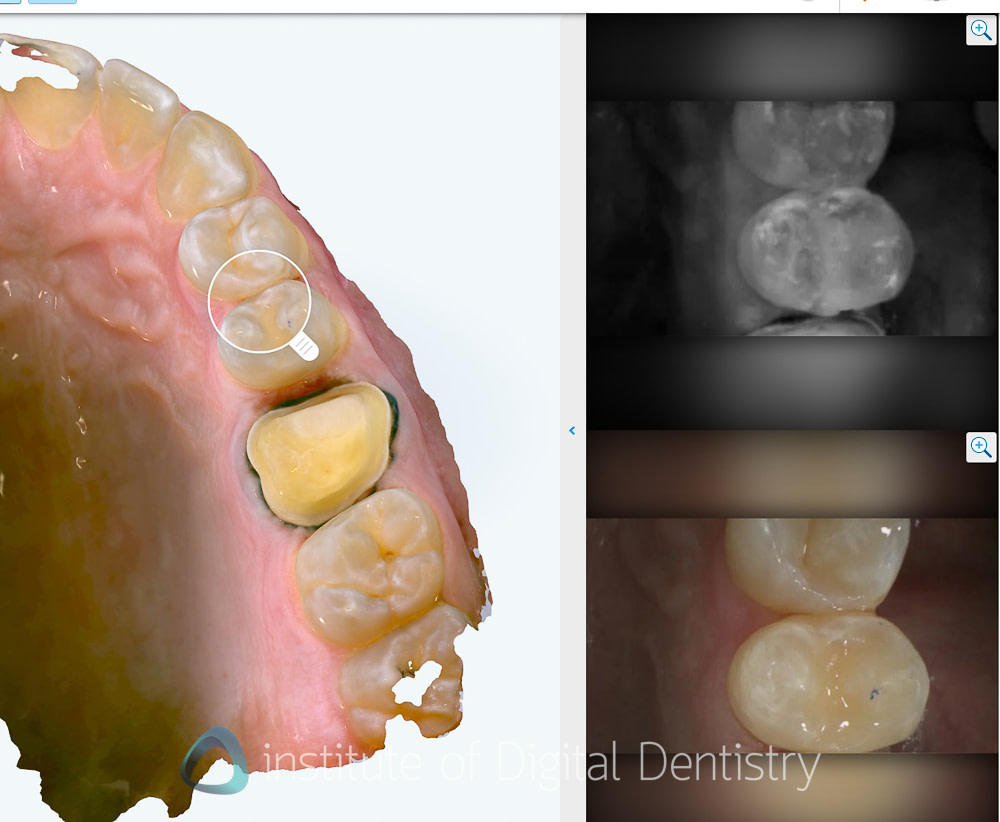

Beyond dimensional accuracy, my favorite part of the Lumina is the scan textures and quality. It produces exceptional final scans. These are the nicest I have seen on the market.

The photorealistic textures are simply unmatched by any other scanner currently available in terms of detail, resolution, and colors. These visuals offer both clinical and communication advantages, and they work well within the extensive range of patient communication apps available within the Align Oral Health Suite.

These scan images really are nice to look at, even for patients. I mean, the detail capture is market-leading, with the scanning picking up even the twists on a ligature tie (see the images below). Gingival texture, tooth characteristics, and restoration details appear with clarity that approaches the quality of intraoral photography. It really is incredible tech.

Integrated Intraoral Camera: High-definition intraoral images are captured while scanning, and multi-angle views of each tooth can be seen. Clinical applications include displaying and tracking gingival health with realistic images.

The UI is very well done here; rather than showing you multiple images, it presents you with a magnifying glass that you can put on any tooth. Then the software shows you the NIRI images and intraoral images captured in that site.